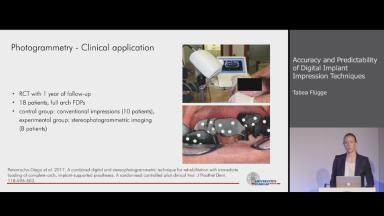

Accuracy and Predictability of Digital Implant Impression Techniques

In her lecture, Tabea Fluegge introduces the systematic review and meta-analysis on the accuracy of different dental impression techniques for implant-supported dental prostheses to which she contributed at the ITI Consensus Conference 2018 in Amsterdam, including the conclusions thereof. She gives an update on the latest developments in intraoral scanning devices and the latest scientific evidence coming from studies that were published after the last Consensus Conference, presenting various new in vitro and in vivo studies. In addition she highlights photogrammetry as a possible alternative to intraoral scanning.

At the end of this Congress Lecture you should be able to…

explain the conclusions of the last ITI Consensus Conference regarding accuracy and predictability of digital implant impression techniques

discuss the latest scientific evidence on the topic

describe another digital alternative to conventional implant impressions